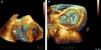

Intraoperative 2D/3D transesophageal echocardiography confirmed rupture of one of the heads of the anterolateral papillary muscle, leading to extensive prolapse of the P1 and P2 segments and causing severe mitral regurgitation (Figures 2 and 3A and B; videos 1, 2 and 3). On surgical inspection, it was observed that the detached muscle head (Figure 4) had become trapped in the left ventricle by a secondary cord attached to the other head. Papillary muscle head reimplantation, mitral annuloplasty with a rigid ring, tricuspid annuloplasty with a Sovering ring and double coronary artery bypass grafting (CABG) (left internal mammary artery to first obtuse marginal and right internal thoracic artery to anterior descending artery) were performed.

Three-dimensional transesophageal echocardiography. (A) Full volume cropped image showing the detached head of the anterior papillary muscle inside the LV (arrow) causing severe prolapse of the posterior leaflet; (B) 3D Zoom of the mitral valve showing prolapse of the P1 and P2 segments. LA: left atrium; LV: left ventricle; Ao: aortic valve; LAA: left atrial appendage.